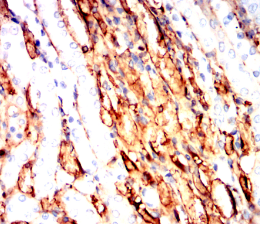

IHC    1/100 - 1/500